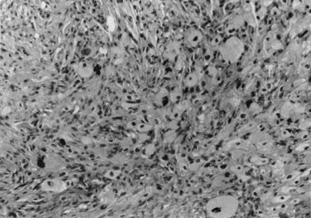

Fig. 13. Erdheim–Chester Disease—This xanthogranulomatous disease is characterized by dermal infiltrate of fibrohistiocytes and Touton giant cells. The histiocytic cells are S-100 negative. (Photos courtesy of William Morris, M.D.)

Histologically, early lesions show a dense collection of histiocytes, some of which have pale, vacuolated cytoplasm. There also is an inflammatory infiltrate of lymphocytes and eosinophils. Mature lesions show the characteristic foam cells and Touton giant cells. Touton giant cells have a central wreath of nuclei surrounded by foamy cytoplasm (Fig. 14). In late lesions, the infiltrate is replaced by fibrosis.